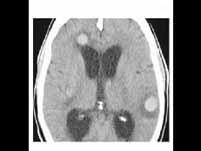

问题 小细胞未分化肺癌脑转移的发生率为()

选项 A.10%左右 B.20%左右 C.50%左右 D.80%左右 E.25%左右

答案 C